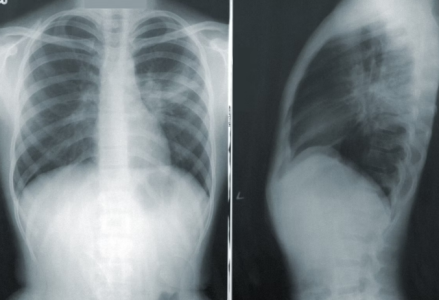

Legionnaires’ disease is a severe bacterial pneumonia that causes lung inflammation and is often deadly when untreated.

The goal of the investigation is to ensure water safety and prevent further exposure. Legionnaires' disease typically begins with flu-like symptoms including fever, headache, muscle aches, and diarrhea.

As it progresses, it may lead to coughing, shortness of breath, chest pain, and even confusion. While most healthy people exposed to Legionella do not fall ill, the disease is especially dangerous for individuals over 50, smokers, and those with compromised immune systems or chronic lung conditions.